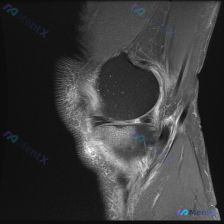

怀疑半月板异常但MRI只看到髌周问题?这个病例帮你理清思路

病例读片分享:临床怀疑半月板异常,MRI却只看到髌周病变

提供的影像为膝盖MRI-T2序列矢状位,切面位于膝关节前部髌股关节区域,图像存在一定截断伪影,未显示后交叉韧带及大部分后侧软组织结构。

影像核心发现

- 髌前皮下软组织水肿:髌骨前方及皮下组织层可见T2高信号影

- 髌股关节腔内积液:髌上囊及髌骨周围关节间隙可见明显条状、片状高信号,提示液体积聚

- Hoffa髌下脂肪垫水肿/炎症:髌韧带深面Hoffa脂肪垫区域可见弥漫斑片状T2高信号,符合水肿或炎症表现

- 股骨远端及胫骨近端骨髓信号未见明确异常,髌骨关节面软骨下仅部分信号不均匀